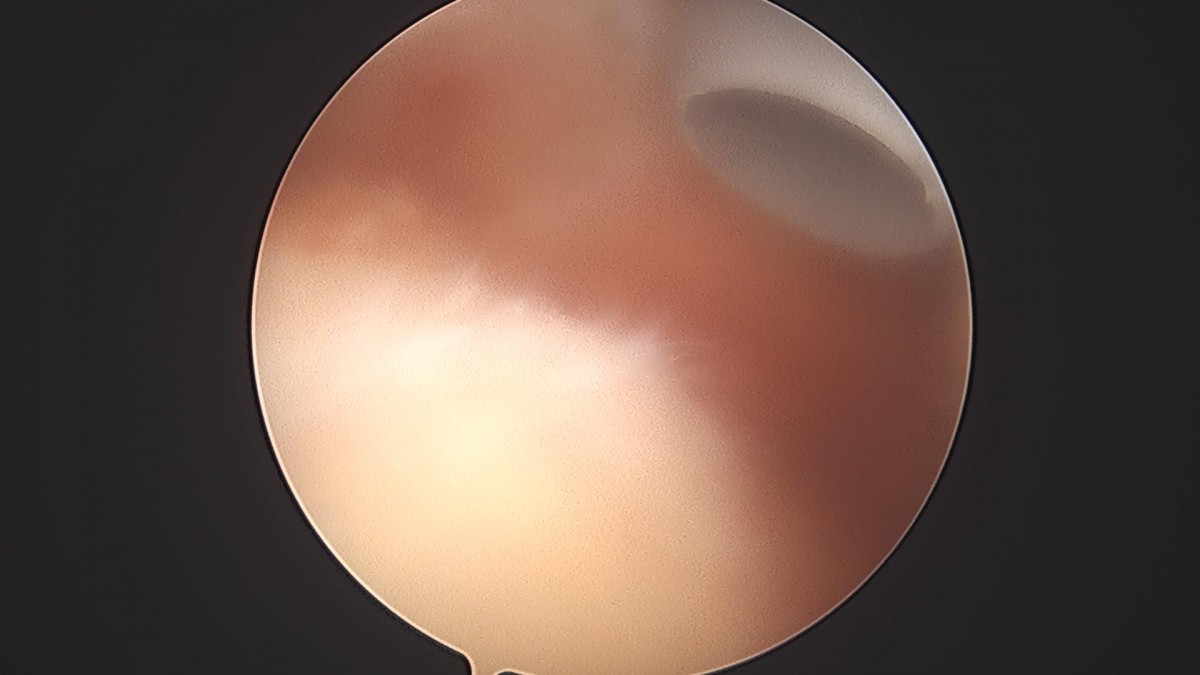

이재상원장님 어깨 견봉하감압술 및 이두박건절제술 류창O 환자